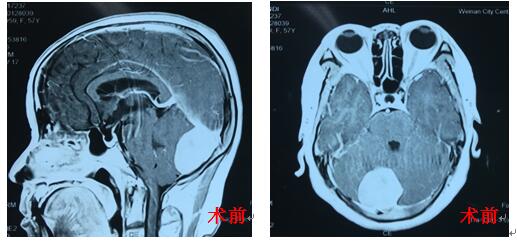

患者苏某,女,52岁,渭南临渭区人, 于数月前行CT检查时发现小脑占位,曾在省内多家医院就诊咨询,经反复考虑后,入住我院神经外科二病区。入院后行颅脑MR平扫及增强提示:小脑镰旁脑膜瘤。我市神经外科首席专家白西民主任医师高度重视,积极进行术前准备,在冯毅副主任医师及朱奕儒住院医师的配合下行小脑镰旁脑膜瘤切除术,术中全切肿瘤,手术顺利。术后病理报告为纤维细胞型脑膜瘤。该患者术后恢复良好,无神经功能障碍。

脑膜瘤虽为良性肿瘤,患者预后较好,但由于此患者肿瘤位于小脑镰旁,紧邻右侧横窦及窦汇,手术难度较大。因此,手术者必须有扎实的神经外科解剖知识、熟练的显微外科技术。本例手术在神经外科二病区医务人员的努力下成功切除肿瘤,使我院在小脑肿瘤的治疗上提高到一个新的高度。